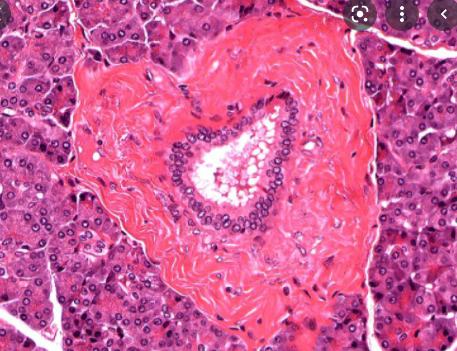

Describe the histology of the pancreas

Pancreatic acini

Islets langerhans

Alpha cells

Beta cells